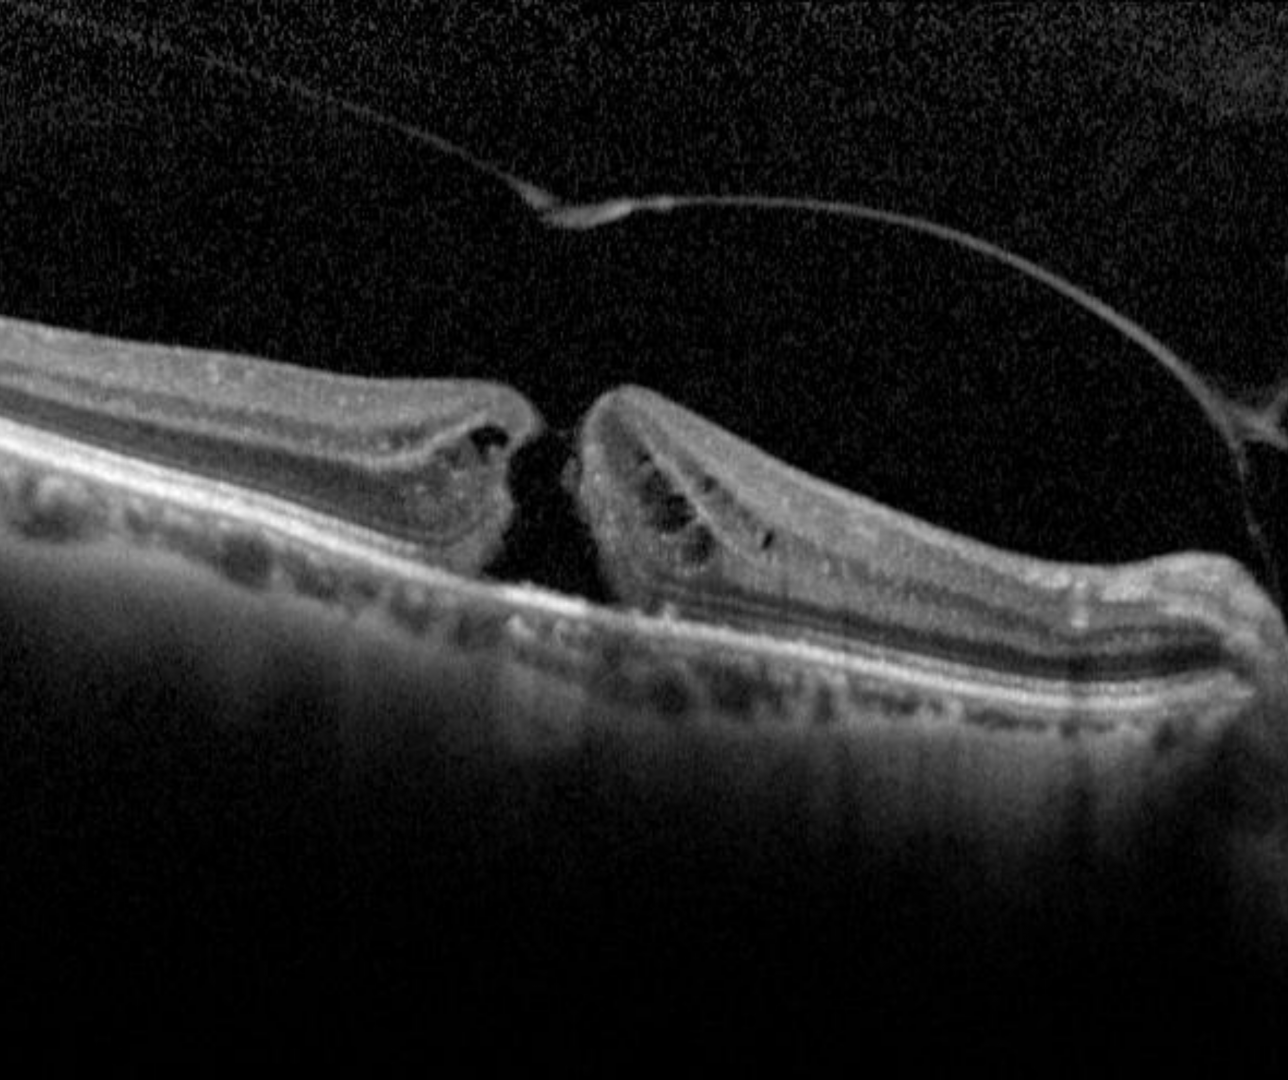

OCT shows loss of all the foveal layers from the internal limiting membrane up to (but not including) the RPE. The edge of the hole is rounded and may contain pseudocysts. The International Vitreomacular Traction Study Classification System for Mitreomacular Adhesion, Traction and Macular Hole developed a classification system for classifying a hole size by OCT measurement of its narrowest aperture.

Small: ≤250µm

Medium: >250µm- ≤400µm

Large>400µm

Case 1: Large FTMH

A 70 year old Asian female with best corrected visual acuity of 6/60 (20/200) - pinhole yielded no improvement.